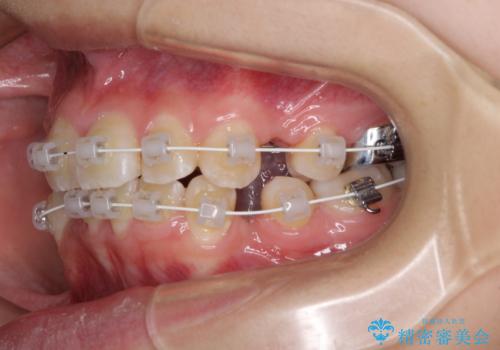

- 上下の八重歯と前歯のデコボコを気にして来院された患者様です。

右上の八重歯が特に著しく、上顎正中が右側にシフトしていました。

デコボコが強いため小臼歯4本を抜歯し、上顎正中を左側に移動させるために補助装置を使用して、ワイヤー装置にて矯正治療を行うこととしました。

正中位置の改善に時間がかかることが予想され、2年半を治療期間の目標としておりましたが、20歳と年齢が若いこともあり、2年2ヶ月で治療を終えることができました。